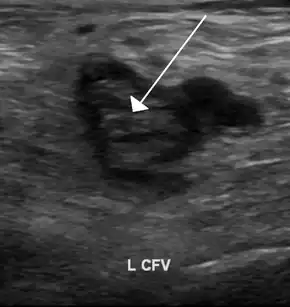

Compression ultrasonography for suspected deep vein thrombosis is the standard diagnostic method, and it is highly sensitive for detecting an initial DVT.[118] A compression ultrasound is considered positive when the vein walls of normally compressible veins do not collapse under gentle pressure.[39] Clot visualization is sometimes possible, but is not required.[119] Three compression ultrasound scanning techniques can be used, with two of the three methods requiring a second ultrasound some days later to rule out the diagnosis.[118] Whole-leg ultrasound is the option that does not require a repeat ultrasound,[118] but proximal compression ultrasound is frequently used because distal DVT is only rarely clinically significant.[117] Ultrasound methods including duplex and color flow Doppler can be used to further characterize the clot[117] and Doppler ultrasound is especially helpful in the non-compressible iliac veins.[119]